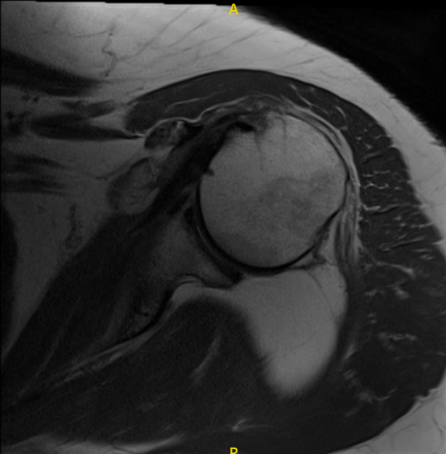

MRI results for her shoulder were also presented and showed full-thickness tear of the supraspinatus tendon spanning 1.4 cm in AP dimension. Tendinosis and partial-thickness articular sided tearing in the infraspinatus tendon spanning 0.8 cm in AP dimension.

Partial tear of the superior subscapularis tendon. Large fatty mass within and deep to the tree’s minor muscle measuring 6.8 x 3.7 x 4.3 cm without patient’s or solid components.

The mass abuts the posterior margin of the glenoid and portions of the posterior aspect of the humeral head and neck. Moderate glenohumeral joint effusion. Undersurface spurring of the acromion with increased risk of subacromial impingement.

MRI Left Shoulder non-contrast